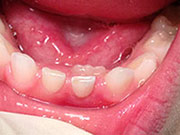

Adult Teeth Coming in Behind Baby Teeth

Baby Teeth - Pediatric Dentistry This is a very common occurrence with children, usually the result of a lower, primary (baby) tooth not falling out when the permanent tooth is coming in. In most cases if the child starts wiggling the baby tooth, it will usually fall out on its own within two months. If it doesn't, then contact your pediatric dentist, where they can easily remove the tooth. The permanent tooth should then slide into the proper place.